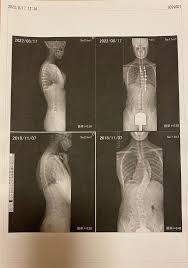

側 弯症側 手術側 ブログ側 ☆延長手術・・・☆側 -側 側わん症:VEPTRの会側 手術が必要な側弯症側 |側 ブログ側 |側 東京都品川の整体なら東京脊柱専門整体院側 側弯症対策!手術を避けるために日常で気をつけること側 |側 大阪市西淀川区佃の整体「なかむら鍼灸接骨院」千船駅徒歩4分側 側弯症コルセット側 術後側 手術が必要な側弯症5選側 -